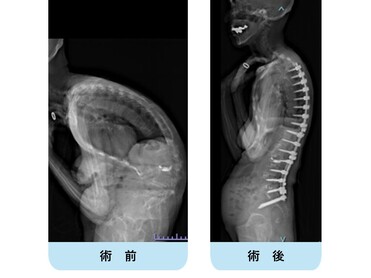

【術前】

典型的な思春期特発性側弯症遺残変形・進行に伴う変性後側弯症・成人脊柱変形の患者さんです。

正面・側面のバランスは破綻していて、難治性腰痛・脊柱管狭窄由来の下肢神経痛のためほぼ寝たきりとなっていました。

【術後】

通常通り侵襲を軽減する目的で腰椎側方経路椎体間固定術、後方矯正固定術を2回に分けて行いました。

正面・側面のバランスは良好で生理的な腰仙椎・体幹のshapeが獲得されています。

腰痛、下肢神経痛は皆無となり、適度の散歩など穏やかな日常生活がおくれるようになりました。